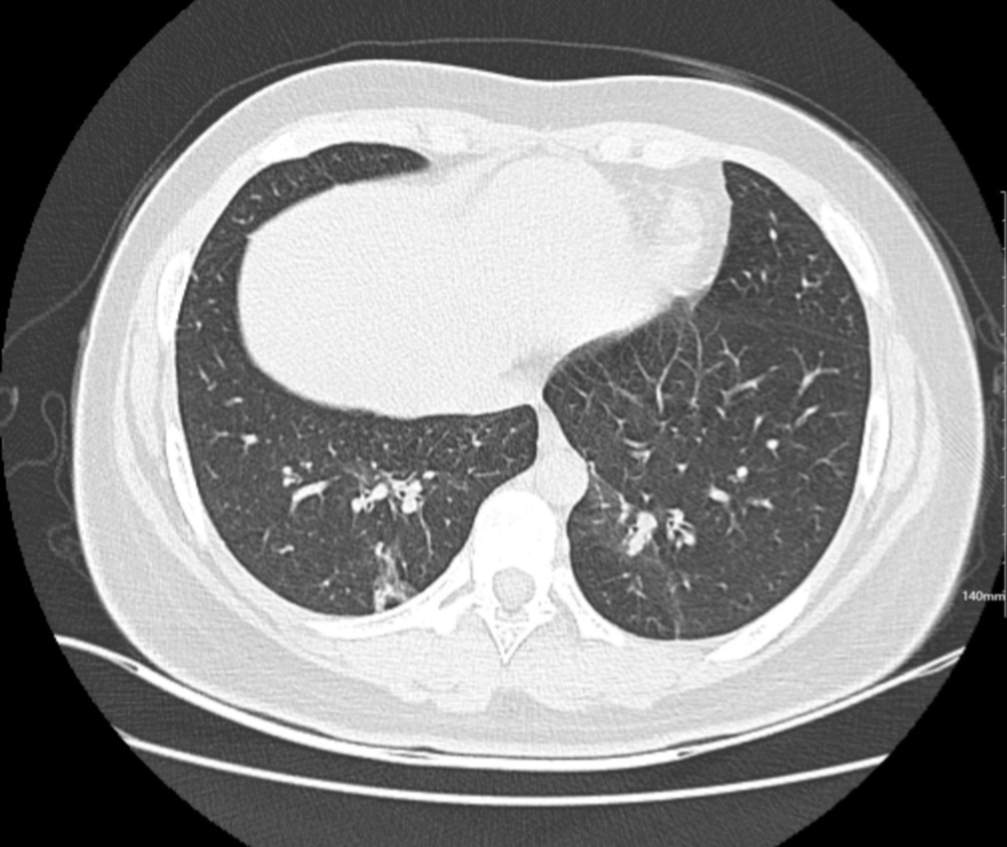

肺部CT:

百日咳肺炎CT 表现

支气管血管束增粗且伴 < 2 个肺叶的磨玻璃密度影, 多提示为单纯性百日咳肺炎。(下图:支气管血管束增粗, 两肺下叶基底段少许磨玻璃密度影)

如出现肺内支气管血管束增粗, 伴≥3 个肺叶斑片影、亚段性实变及支气管气象时, 提示患儿病情较重,可能合并其他感染。